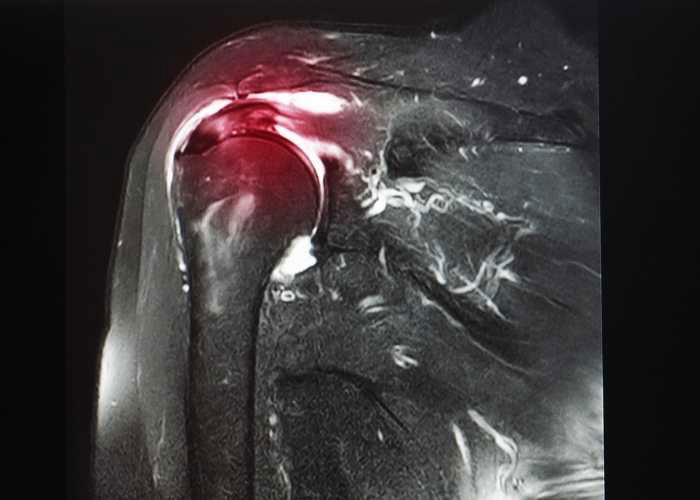

MRI T2 mapping of the asymptomatic supraspinatus tendon by age and imaging plane using clinically relevant subregions Gallery MRI T2 mapping of the asymptomatic supraspinatus tendon by age and imaging plane using clinically relevant subregions Rotator Cuff MRI T2 mapping of the asymptomatic supraspinatus tendon by age and imaging plane using clinically relevant subregionsCategories: Rotator Cuff|Tags: Glenohumeral Instability Repair, Rotator Cuff Tear Repair|